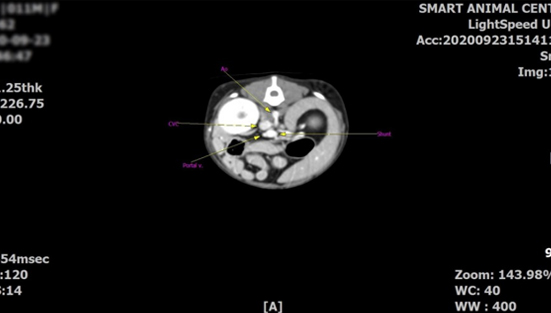

뇌의 질환

염증성 및 감염성 뇌염 (괴상성 뇌수막염, 육아종성 뇌수막염, 각종 감염에 의한 질환 등)

구조적 이상 (후두공 이형성증, 뇌수두증 등)

뇌종양